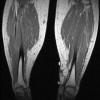

History:  The patient was a 44 year-old woman who complained of a 3 cm hard mass in her ankle at the medial aspect of her tibia. She had a mass that was removed from that area approximately about 3 years ago and the diagnosis was lipoma. She developed postoperative infection with a prolonged course and was treated. On physical examination, the mass was hard like a stone and was thought to be mineralized. MRI revealed fat density in the mass. The current mass was excised and yielded the this specimen.

MRI: There is an oval mass with fat density in the left ankle. The mass is very well demarcated from the surrounding tissue without evidence of invasion into the surrounding tissue.

MRI